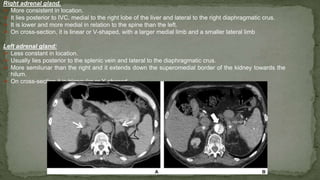

Right adrenal gland.

➢ More consistent in location.

➢ It lies posterior to IVC, medial to the right lobe of the liver and lateral to the right diaphragmatic crus.

➢ It is lower and more medial in relation to the spine than the left.

➢ On cross-section, it is linear or V-shaped, with a larger medial limb and a smaller lateral limb

Left adrenal gland:

➢ Less constant in location.

➢ Usually lies posterior to the splenic vein and lateral to the diaphragmatic crus.

➢ More semilunar than the right and it extends down the superomedial border of the kidney towards the

hilum.

➢ On cross-section it is triangular or Y-shaped.